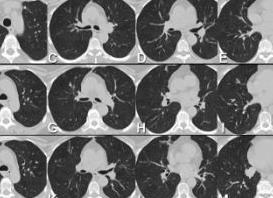

При прохождении рентгеновских лучей происходит частичное поглощение излучения тканями человека в зависимости от плотности. Специальные датчики фиксируют это ослабление и передают информацию компьютеру. Программное обеспечение формирует объемное изображение исследуемой ткани и выдает результат в виде послойных черно-белых снимков изучаемой области с шагом 1 мм в разных проекциях. В последнее время получает распространение более точный вид КТ – мультиспиральная компьютерная томография с шагом срезов 0,5 мм.

Расшифровку результатов должен сделать врач-рентгенолог, изучая изображение на экране монитора, он имеет возможность оценить состояние всех внутренних систем, тканей и органов грудной клетки. Снимки при этом делаются тонкими срезами, что позволяет исследовать орган в разных плоскостях. Если сравнить КТ с аналогичными методами, то его однозначно можно считать более информативным, подробным и менее вредным для здоровья человека.

На КТ грудной клетки четко видно:

- повреждения костной системы (трещины, переломы), ранения, инородные тела;

- абсцессы, воспаления;

- болезни сердца, аорты;

- кровоизлияния, кровотечения;

- аномалии развития внутренних органов;

- онкологические заболевания;

- доброкачественные опухоли;

- воспаления хрящевой ткани, межпозвоночные грыжи;

- заболевания лимфоузлов;

- стеноз пищевода;

- пневмонию, затемнение в легких.

Томография с контрастом отчетливо визуализирует сосудистые патологии, атеросклеротические бляшки, очень маленькие опухоли, инфаркты, гематомы.

У женщин КТ грудной клетки дает полноценную картину изменений в молочной железе, наличия неоднородных уплотнений, кист, воспалений.